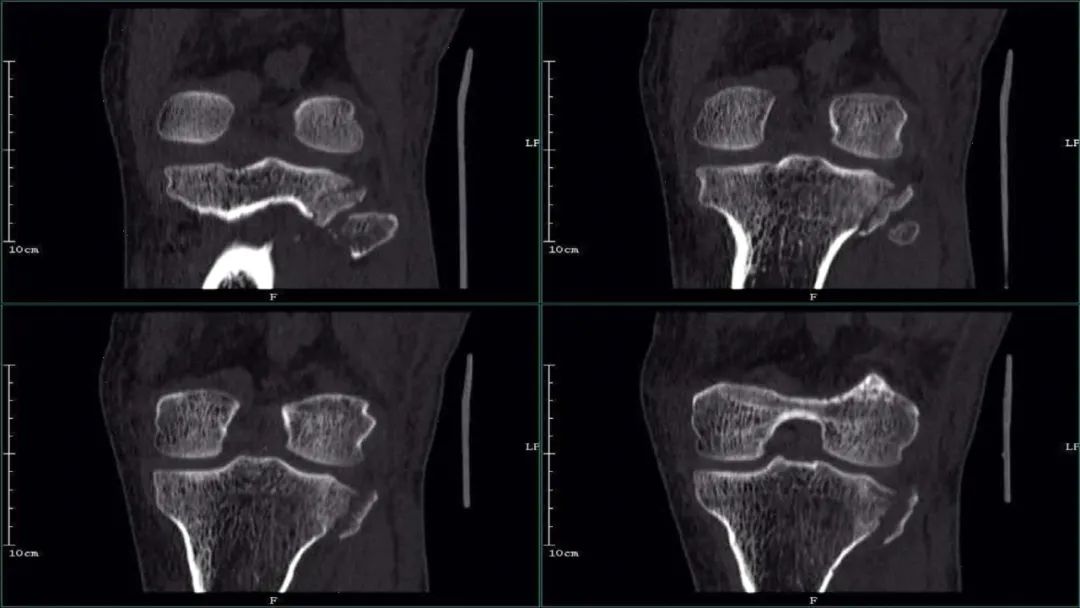

Ⅴ型:涉及内、外侧平台劈裂的双髁骨折:

简要病史:患者,女,50 岁,车祸外伤致左膝关节疼痛。

②CT 医学百科网 | YxBaike.Com

医学百科网 | YxBaike.Com

X 线及 CT:胫骨平台内、外侧平台骨皮质均不连续,见多发骨折线影,胫骨干与干骺端未分离。 医学百科网 | YxBaike.Com